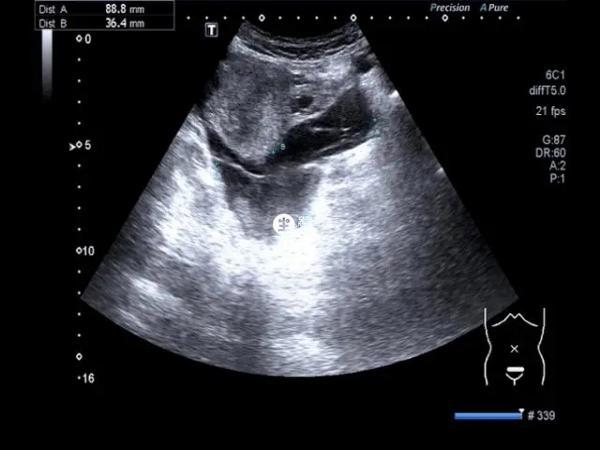

女性怀孕后一个月左右,体内就会形成卵黄囊,它的出现代表着胚胎发育的很正常,若是在一个月左右的时候没有发现卵黄囊,那么胎儿发育就有一定的问题,在怀孕期间可以通过卵黄囊判断女性是宫内孕还是宫外孕,在发现卵黄囊1-2周内,就会长出胎心胎芽,这也是胎儿正常发育的一个标志,但是有的女性发现卵黄囊的时间比较早,有的则是比较晚,如果一直都没有检查到,说明有胎停的风险。

卵黄囊一般是怀孕早期用来衡量胎儿发育状况的重要参照标准,因为卵黄囊是胎儿和母体进行营养交换的重要场所,只有出现了卵黄囊,胎儿才会进一步的发育生长,也只有出现了卵黄囊,才表示胎儿发育正常。

卵黄囊是孕早期孕囊生长发育的重要结构,由胚外内胚层和胚外中胚层组成,可以储存、分解、吸收和输送营养物质,对于早孕期孕囊生长发育有着重要的作用。

在正常的情况下,精子和卵子结合后,会形成受精卵,而受精卵只要着床在宫腔壁上,就能确定是怀孕,随着受精卵进一步的发育,会出现孕囊,而孕囊再进一步发育,就会出现卵黄囊,而卵黄囊出现后,主要是能说明以下几方面的问题: